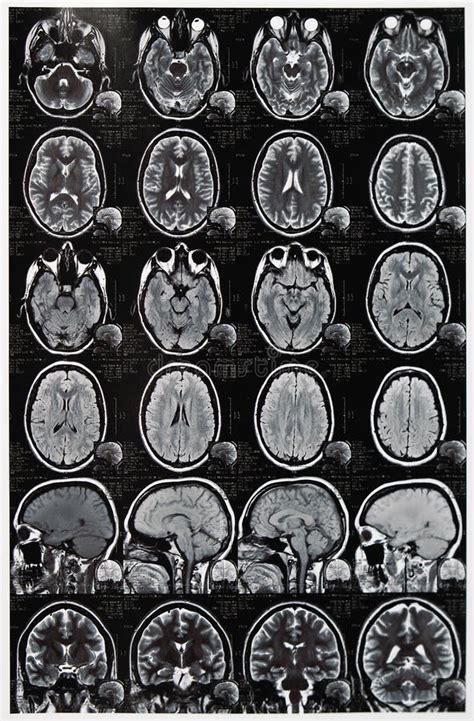

RMN Cerebral

Durerile de cap recurente sau alte simptome neurologice pot indica afecțiuni ale creierului sau probleme sistemice.

Tractografie RMN

Tractografia RMN este o metodă imagistică avansată bazată pe rezonanța magnetică de difuzie (DTI - Diffusion Tensor Imaging), care permite vizualizarea și reconstrucția tridimensională a fasciculelor de fibre nervoase din creier. Această tehnică este esențială pentru înțelegerea conexiunilor neuronale și pentru planificarea intervențiilor neurochirurgicale.

Când se Indică Tractografia RMN?

- Afecțiuni neurologice și neurochirurgicale: Planificarea intervențiilor chirurgicale pe creier (pentru a evita lezarea tracturilor nervoase importante); evaluarea tumorilor cerebrale și a raportului acestora cu fasciculele nervoase; monitorizarea pacienților după intervenții neurochirurgicale.

- Afecțiuni cerebro-vasculare: Accident vascular cerebral ischemic sau hemoragic; leziuni ischemice subclinice; evaluarea reabilitării neurologice după AVC.

- Afecțiuni traumatice: Traumatisme cranio-cerebrale și afectarea tracturilor nervoase; evaluarea consecințelor posttraumatice (tulburări de memorie, atenție, coordonare).

- Boli neurodegenerative și alte tulburări: Scleroza multiplă și alte boli demielinizante; epilepsie; demențe și tulburări cognitive; tulburări de dezvoltare neurologică.

Spectro-RMN (Spectroscopie prin Rezonanță Magnetică)

Studiul Spectro-RMN (spectroscopia prin rezonanță magnetică) este o metodă imagistică avansată care permite nu doar vizualizarea structurilor anatomice, ci și analiza compoziției chimice a țesuturilor. Această tehnică oferă informații suplimentare față de RMN-ul clasic, fiind utilă în special în diagnosticul și monitorizarea afecțiunilor neurologice, oncologice și metabolice.

Când se Indică Studiul Spectro-RMN?

Spectroscopia RMN este recomandată pentru evaluarea:

- Afecțiuni neurologice: Tumori cerebrale (diagnostic diferențial între leziuni benigne și maligne); monitorizarea tumorilor cerebrale postoperator sau după radioterapie; epilepsie (identificarea zonelor de origine); demențe și boli neurodegenerative; leziuni demielinizante.